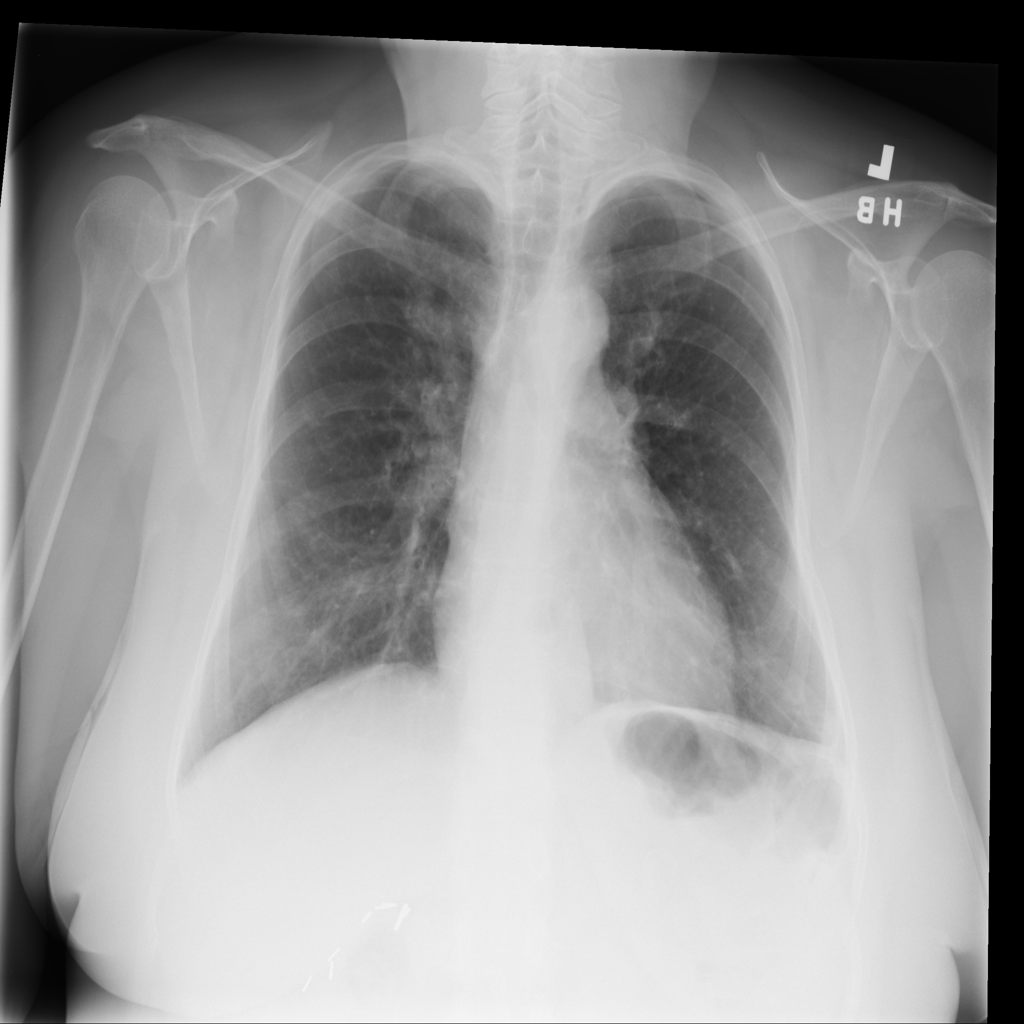

PAT-4F7E · IMG-000Hernia

PAT-4F7E · IMG-000

PA